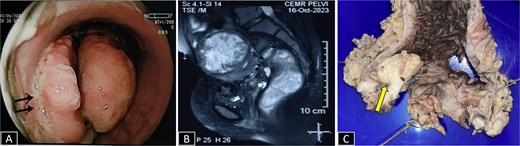

A 37-year-old female presented with a 2-year history of non-cyclical, recurrent rectal bleeding, significant weight loss, altered bowel habits, and spontaneous passage of polypoid tissue per rectum. Advanced imaging modalities, including computed tomography scan and contrast-enhanced MRI, demonstrated an aggressive local disease pattern with transmural rectal wall thickening, mesorectal fat stranding, and loss of intervening fat planes, features favoring a malignant lesion (Fig. 1A and B). Despite extensive diagnostic workup, including multiple biopsies, findings remained inconclusive, limited to nonspecific granulation tissue, inflammatory changes, and hyperplastic or adenomatous polyps with low-grade dysplasia. Pelvic imaging also revealed uterine fibroids and adnexal abnormalities. Ongoing diagnostic uncertainty necessitated a lower anterior resection with diversion loop ileostomy, which was complicated by persistent postoperative purulent discharge and poor clinical recovery, Gross examination of the resected rectal segment showed a diffusely thickened wall with multiple mucosal ulcerations and a well-circumscribed polypoid lesion measuring 3 cm in maximum dimension (Fig. 1C). Histological evaluation revealed ulceration with granulation tissue, along with multiple foci of ectopic endometrial glands and stroma within the submucosa and muscularis propria. Immunohistochemistry (IHC) confirmed the endometrial origin, with strong estrogen receptor (ER) positivity in both the glands and stromal component (Fig. 2). These findings confirmed the rare diagnosis of polypoidal rectal endometriosis, illustrating the protean clinical and pathological manifestations of the disease and its potential to mimic malignancy, leading to significant diagnostic delay.

(A) Micrograph from initial rectal polyp biopsy showing complete mucosal ulceration with underlying inflammatory granulation tissue (H&E 100×). (B) Micrograph from resection specimen showing colonic mucosa with ectopic endometrial glands and stroma traversing transmurally from the lamina propria to muscularis propria (H&E 200×). (C) Endometrial glands and stroma highlighted by estrogen receptor (ER, IHC 200×).